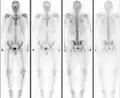

Normal bone scan in a person with osteopoikilosis